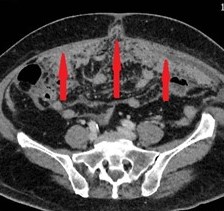

Mesenteric root infiltration — Absolute contraindication for cytoreductive surgery (Courtesy Dr. V. Penopoulos)